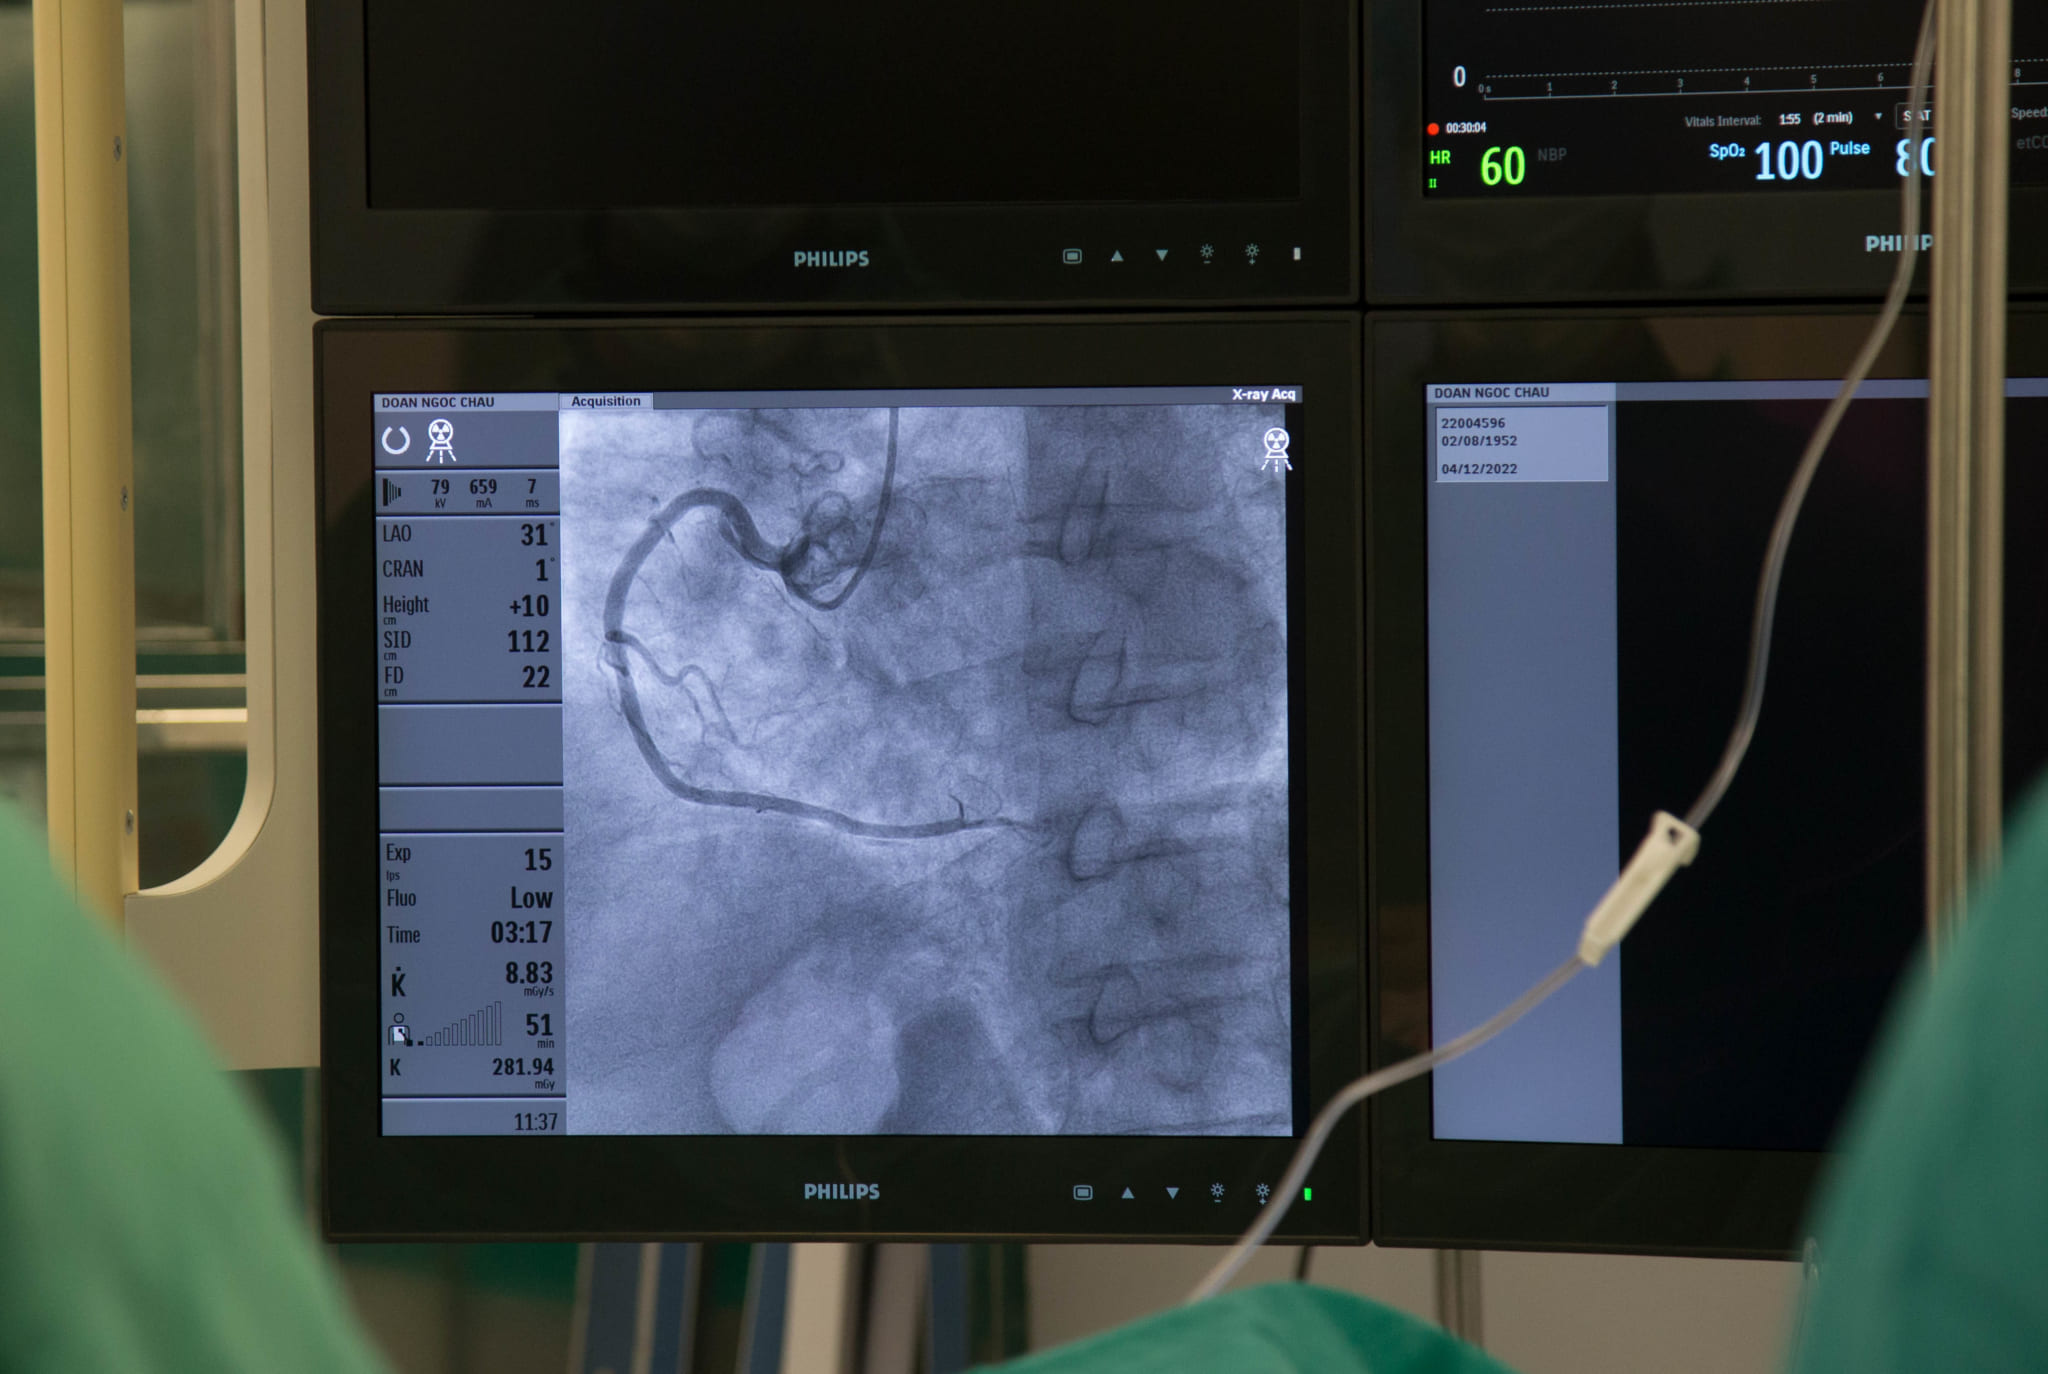

Cũng ngay trong sáng ngày 12/4, kỹ thuật chụp động mạch vành qua da đã được Ths.BS Vũ Học Huấn – Trưởng Khoa Tim mạch, Đột quỵ thực hiện thành công trên 5 bệnh nhân dưới sự hướng dẫn, hỗ trợ, chuyển giao kỹ thuật trực tiếp từ các chuyên gia của Bệnh viện Đại học Y Hà Nội.

Trường hợp bệnh nhân vào viện với cơn đau thắt ngực ngắn trên nền có nguy cơ tăng huyết áp, đái tháo đường, rối loạn mỡ máu và tuổi cao. Bệnh nhân được chỉ định thực hiện kỹ thuật chụp động mạch qua da, phát hiện những tổn thương; từ đó có những theo dõi, điều trị, kiểm soát các yếu tố nguy cơ và thay đổi lối sống phù hợp.

Kỹ thuật chụp động mạch vành qua da được thực hiện tại Bệnh viện đa khoa Quốc tế Hải Phòng đã ghi nhận kết quả tốt. Đây được coi là tiêu chuẩn vàng trong chẩn đoán chính xác bệnh lý mạch vành. Đặc biệt, nếu có tổn thương ý nghĩa sẽ được can thiệp, xử lý triệt để. Cạnh đó, hệ thống với tối ưu liều chiếu tia, giúp hạn chế thấp nhất sự ảnh hưởng với bệnh nhân mà vẫn đảm bảo chất lượng hình ảnh chụp.